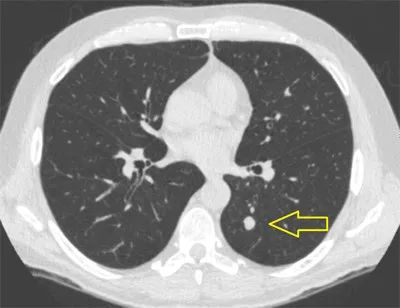

6. X线胸片和(或)胸部CT检查异常者  包括肺不张、肺部结节或团块影、阻塞性肺炎、炎症吸收不理想、肺部弥漫性病变、肺门或纵隔淋巴结肿大、气管支气管狭窄以及原因未明的胸腔积液等异常改变者。